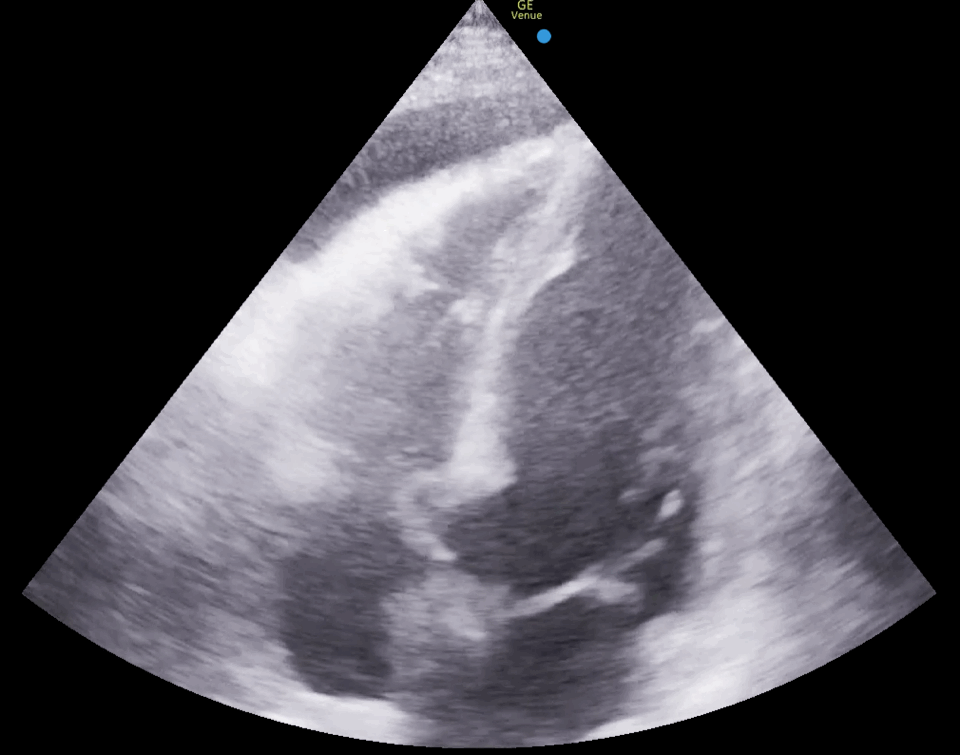

PLAX

PLAX view showing pericardial effusion with hematoma and compromised right ventricular filling: PLAX view, taken from a patient after cardiac surgery with moderate hemodynamic instability, shows a pericardial effusion surrounding the heart. A grey mass is visible within the effusion, located between the liver and the right ventricle, representing a hematoma. The right ventricle shows reduced filling during diastole, indicating compromised function, and the findings urge prompt treatment to prevent further deterioration.